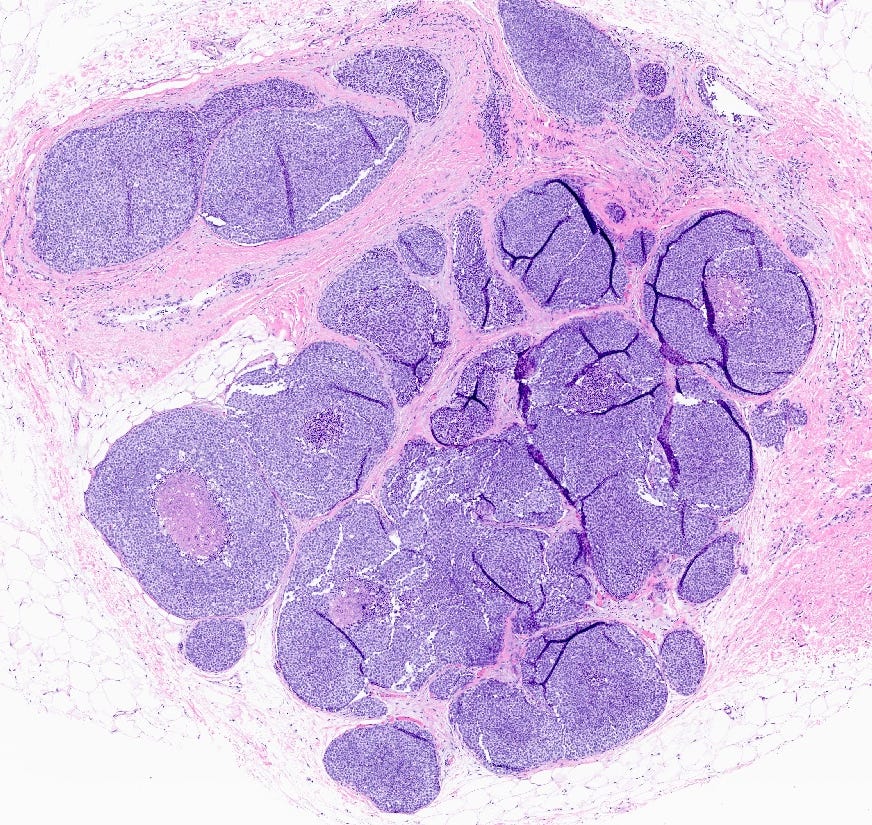

Florid lobular carcinoma in situ - microscopic images

Florid LCIS is a rare (< 5% of LCIS) nonclassical or variant form of lobular carcinoma in situ in which acini and ducts are markedly distended with little to no intervening stroma. It may have a mass-like architecture and includes cells with cytologic features of classic LCIS (type A or type B cells) with or without comedonecrosis and calcifications. Most cases are associated with classic LCIS or atypical lobular hyperplasia (ALH).

Florid LCIS has features of a high risk precursor lesion of invasive carcinoma including a higher upgrade rate, increased association with invasive carcinoma and more genetic complexity compared to classic LCIS.

In contrast to classic LCIS, complete surgical excision of florid LCIS is recommended.